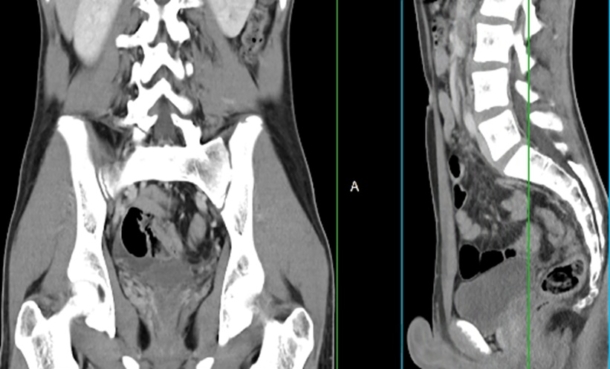

Radiology

Early Health Technology Assessment to Detect Incidental Pulmonary Embolisms on CT